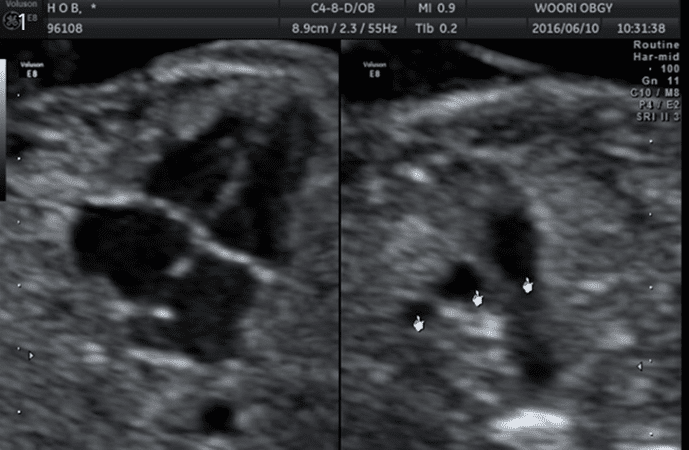

태아 후경부투명대(NT)검사

태아의 기형을 진단하는 기본 초음파검사이며 예약이 필요합니다. 임신 11-13주 사이에 태아의 후경부투명대 두께를 측정하여 태아의 기형아 위험도, ‘다운증후군’ 및 심장기형 등을 알아내는 검사입니다.